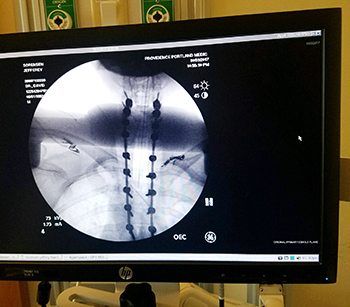

Following an MRI of my head and spine, I was told I had a tumor on my spinal cord – a myxopapillary ependymoma. The tumor started at C2 and extended to T6 and is considered one of the largest of its type ever recorded. It’s likely to have been growing since I was a young child. In order to be removed from my body, nine vertebrae had to be cut and therefore I am now fused from C3 to T5 (see attached MRI scan).